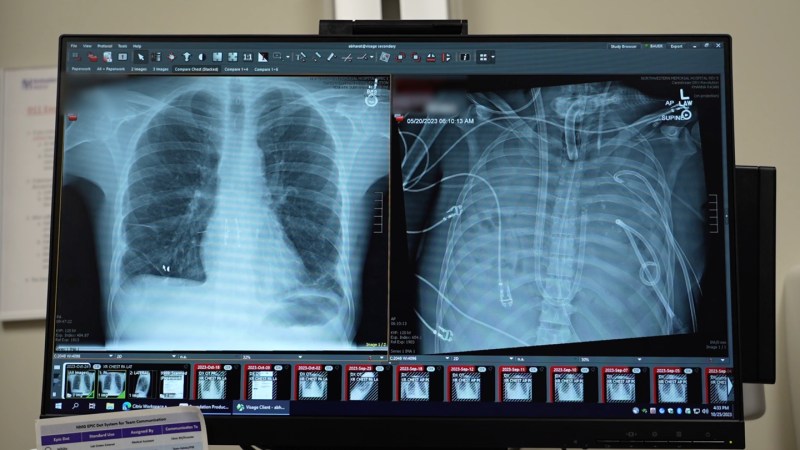

A new artificial lung system might keep people without lungs alive for weeks. Like real lungs, tubes and pumps oxygenate blood and maintain blood flow.A new artificial lung system might keep people without lungs alive for weeks. Like real lungs, tubes and pumps oxygenate blood and maintain blood flow. Read More